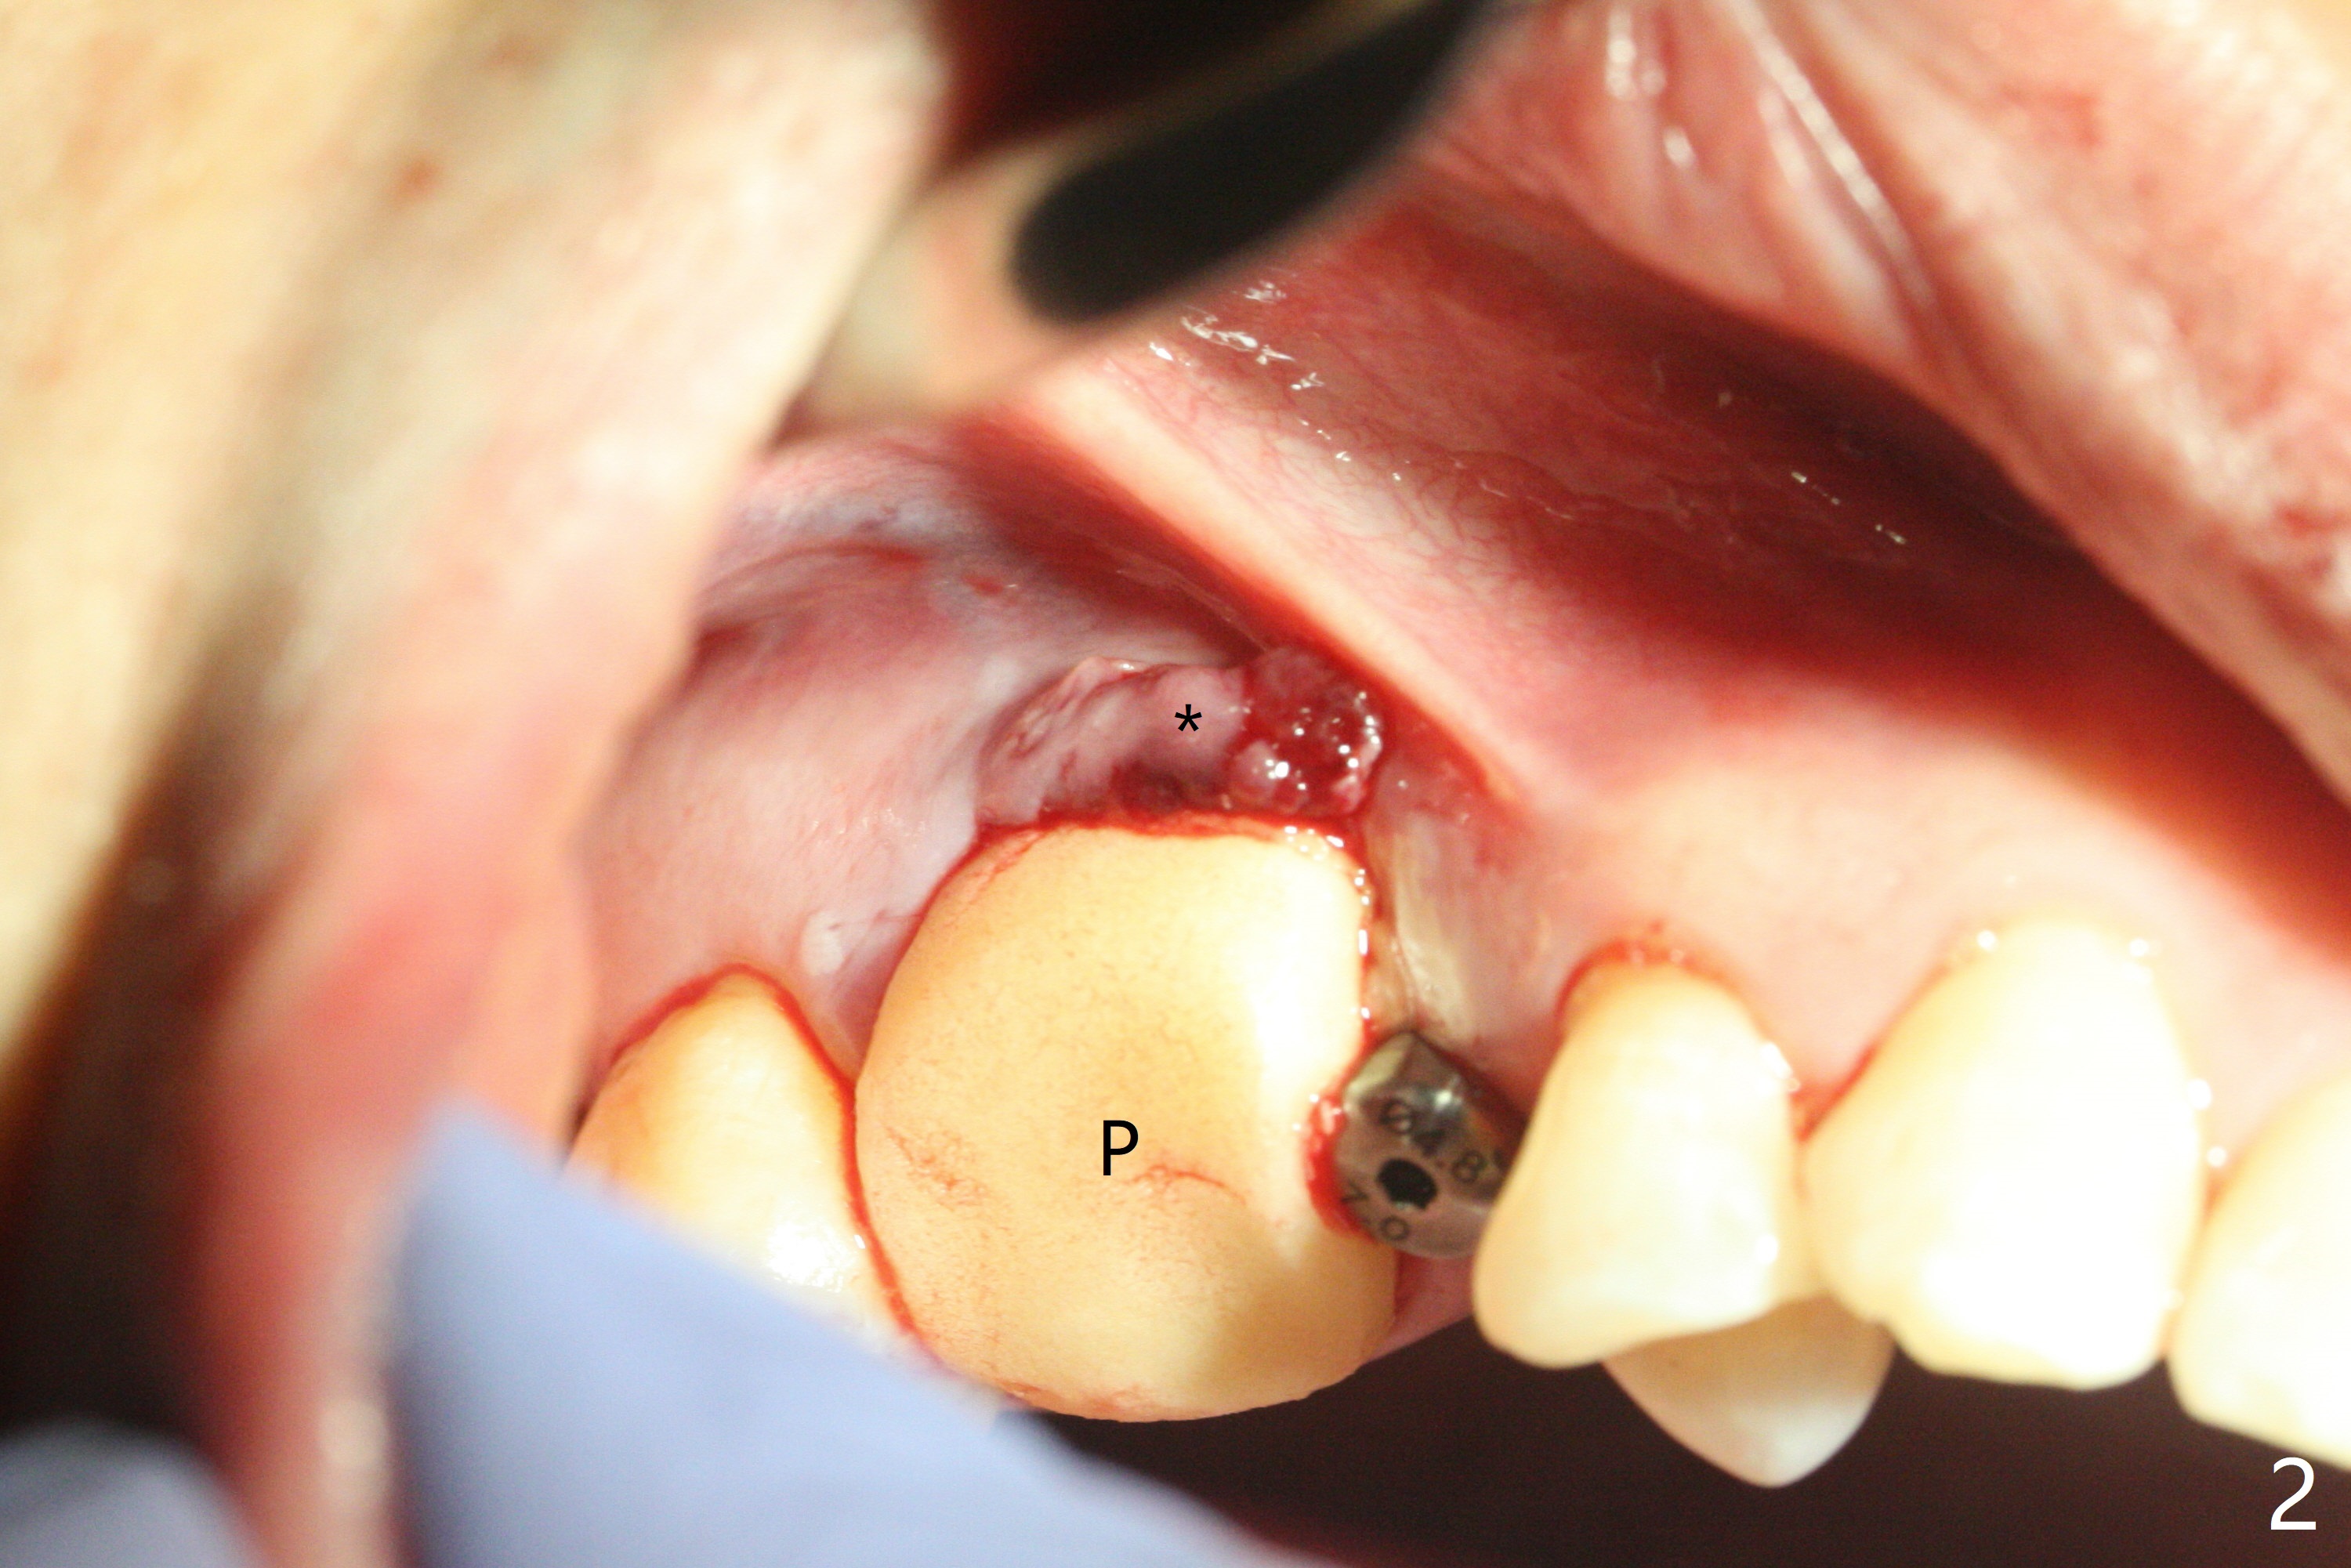

When the tooth #3 with severe buccal gingival recession is extracted and implants are placed at #3 and 4 with guide, sticky bone in 2 large pieces is packed between these implants with a previously large defect in a seemingly secure manner (Fig.1 *). Use of a longer implant at #3 (11.5 mm vs. 10 mm) will reduce the chance of abutment screw loosening in the future. With 2 pieces of PRF membrane coverage, an immediate provisional is fabricated for graft retention (Fig.2,3 P). To stabilize a buccal flap (Fig.2 *, used to be buccal furca gingiva), periodontal dressing is applied later. The buccal socket heals 12 days postop (Fig.4). Apparently new bone forms between the implants 4 months postop (Fig.5). The abutment at #3 may not be completely seated. In fact it is loose, probably related to buccal gingival and gingival cuff erythema 6.5 months postop (Fig.6). Large healing abutments are placed to form the interdental (interimplant) papilla without effect (*). Provisional crowns will be fabricated for the papilla formation. When cemented abutments are placed (Fig.7), papilla formation by manipulation of provisional crowns seems unlikely. Impression is taken. Although there is no implant thread exposure, the buccal plate is concave 7.5 months postop (Fig.8). With special crown design, food impaction should be minimal post cementation (Fig.9,10). There is no bone loss 5.5 months post cementation (Fig.11), while the soft tissue is healthy (data not shown).